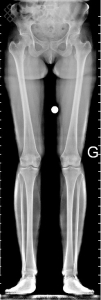

TéléRadiographie des Membres Inférieurs

Vous serez installés en position verticale avec les pieds joints.